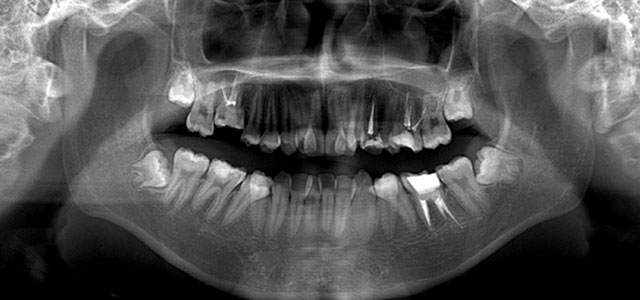

矯正前 パノラマX線

主訴 凸凹の歯並びを治したい。虫歯が多い。

年齢 10代男性

治療法 上下顎マルチブラケット装置

抜歯の有無 上顎左右第一大臼歯、上顎左側第一小臼歯、下顎左右側第一大臼歯

治療期間 2年5ヶ月